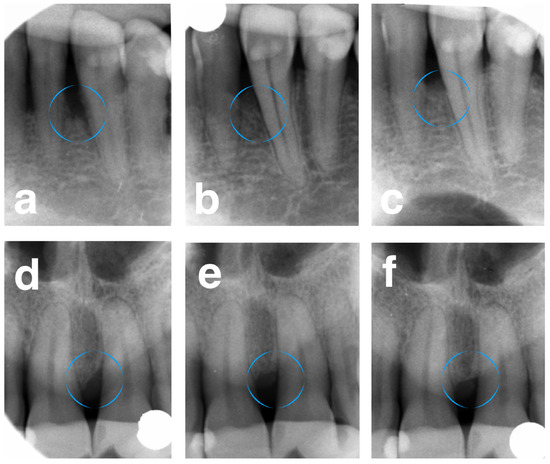

2.4. Radiographic Measurements

- CEJ-BD: the distance from the CEJ to the bottom of the defect;

- CEJ-AC: the distance from the CEJ to the interdental bone crest;

- DD: the distance from the spot where the AUX2 crossed the CEJ–BD line to the BD;

- Radiographic angle: the angle between the AUX1 and AUX2 of the treated tooth.